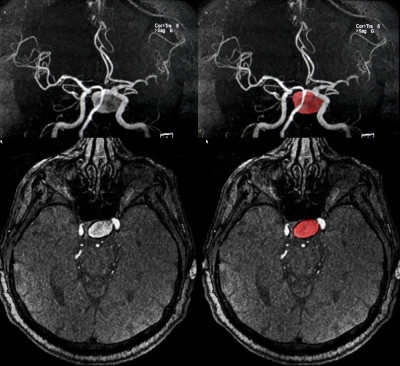

No matter how you look at brain aneurysms or strokes, they’re not good news. While some of the symptoms are similar, it’s a race against the clock for medical professionals to determine what they’re dealing with to limit the damage. Both of these medical events can cause weakness in muscles and vision problems, but there […]

Would you realize if you, or someone you loved, was suffering a brain aneurysm? We’ve created a list of 5 facts and symptoms of a brain aneurysm.